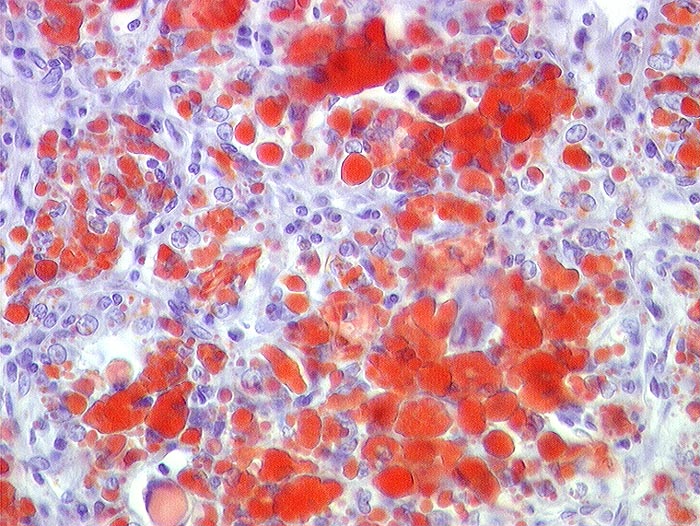

PathoPic ID 22 - Nierenzellkarzinom: intrazellulärer Lipidnachweis

Nierenzellkarzinom: intrazellulärer Lipidnachweis

Mit Sudanrot angefärbte intrazelluläre Lipidtropfen in einem hellzelligen Nierenzellkarzinom

gelber Tumor (Lipid!) mit Einblutungen

Nierenzellkarzinom pT1. Zufallsbefund anlässlich Sonographie nach Unfall.